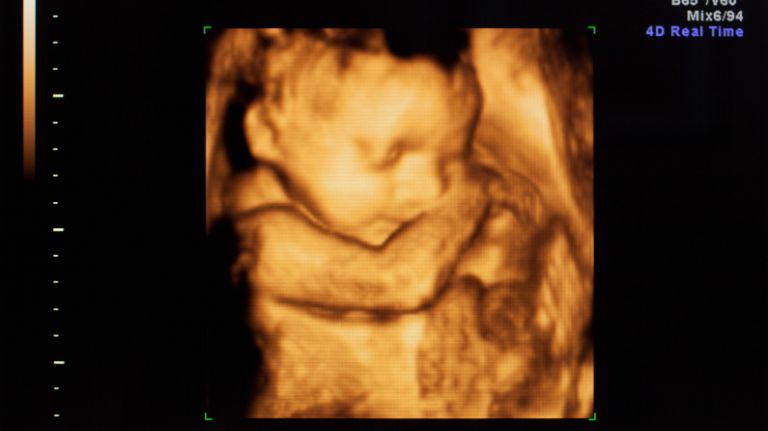

It didn’t start with the unwatchable Planned Parenthood videos circulating around the Web, although they’re unquestionably bolstering the anti-abortion cause. The phenomenon began, arguably, with the modern sonogram, which inarguably shows well-formed babies where protoplasmic blobs once were said to be.

It’s hard to ignore a 3-D or 4-D sonogram showing a baby girl laughing at 24 weeks. It has to be downright haunting to surgically exact a fetus from the womb after seeing his face in picture-perfect detail at 14 weeks.

Prenatal photography has to have a lot to do with that.

Those pictures will not be ignored.